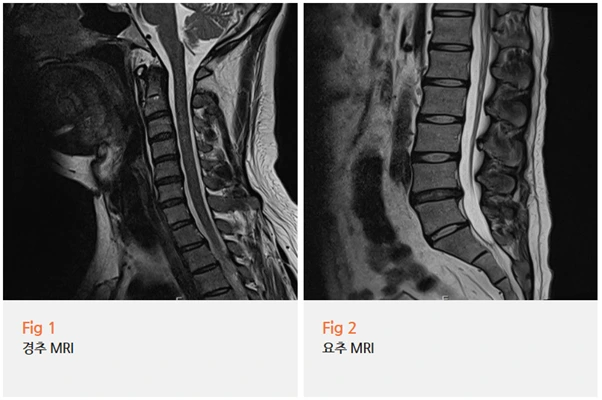

더 상세히 보기 위해,

뇌 MRI와 자율신경계 기능 검사를 진행했는데요.

다행히 뇌질환은 배제됐고,

자율신경 기능 이상이 동반된 경추성 두통으로 진단됐어요.

경추성 두통이라는 게 생각보다 복잡해요.

단순히 목이 아픈 게 아니라

신경통, 어지럼증, 흐릿한 시야, 안면통증,

불면, 불안 같은 자율신경 증상까지 다 동반될 수 있거든요.

그리고 문제는 영상 검사에서 명확한 병변이

잘 안 나타나는 경우가 많다는 거예요.

그래서 진단이 어렵고, 환자분들도 이 병원 저 병원 전전하시는 경우가 많죠 ;;